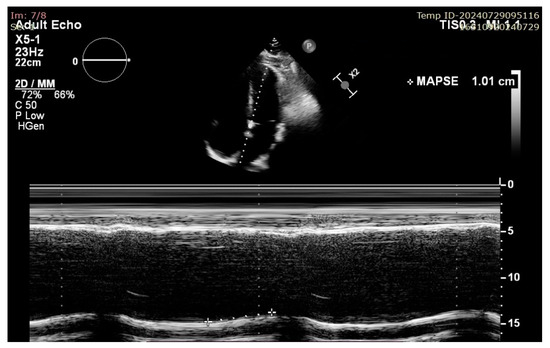

Mitral Annular Plane Systolic Excursion (MAPSE): A Review of a Simple and Forgotten Parameter for Assessing Left Ventricle Function